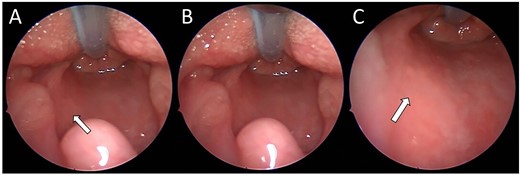

(A) Endoscopic (MLB) photographs of the supraglottic region. (B–C) Endoscopic (MLB) photographs of glottic and subglottic regions highlighting the presence of a subglottic haemangioma.

A 13-week-old child was acutely referred to the tertiary paediatric ENT team with stridor. The child had altered breathing for 2 weeks, initially treated as croup. On admission, the child had a tracheal tug, intercostal recessions and significant stridor. A 10 cm facial cutaneous plaque haemangioma was noted. Intravenous dexamethasone was commenced and micro-laryngoscopy showed a subglottic haemangioma occupying 40% of the airway, equivalent to Myer-Cotton classification Grade 1 (Fig. 1). Oral propranolol was commenced at 1 mg/kg/day in three divided doses as per local protocol increasing to 2 mg/kg/day once treatment was established. No neck lesion was apparent on clinical examination.

(A–C) Intra-operative endoscopic photographs highlighting the left sided asymmetric parapharyngeal fullness immediately inferior to the inferior pole of the left tonsil where the biopsy was undertaken and macroscopically abnormal tissue identified.

On review of the imaging, the child underwent a biopsy of the lesion for a tissue diagnosis. Direct inspection revealed bulging of tissue from the left parapharyngeal space (Fig. 3). The mucosa was incised, constrictor muscles were divided and incisional biopsies were obtained. Histopathology samples showed lobules of haemangioma, strongly positive for GLUT-1 on immunohistochemistry confirming a carotid sheath infantile haemangioma. The patient continues to be followed up in the outpatient setting.